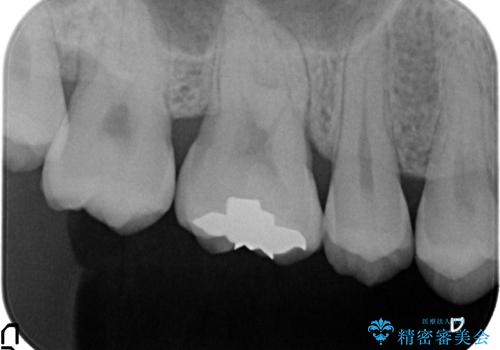

- 右上6番目の歯がしみるので診て欲しいといらっしゃった方の症例です。

古い樹脂が欠けており、そこから虫歯になっていたため、PGA(ゴールド)インレーによる修復を行いました。

- PGA(ゴールド)インレー…¥60,000費用は治療当時の料金となります